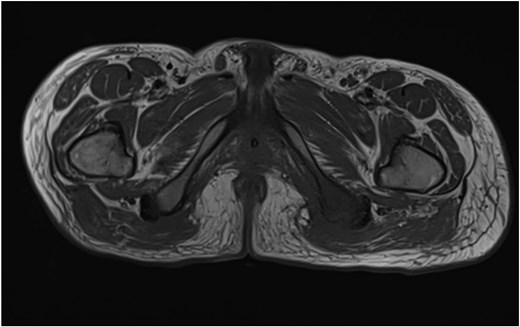

He was admitted to the Plastic and Reconstructive Surgery service for investigation and multidisciplinary management. Initial blood tests demonstrated mild anaemia, mildly elevated white cell count. His C reactive protein was 39. Liver and renal function tests were normal. Magnetic resonance imaging (MRI) demonstrated features of osteomyelitis within the left ischial tuberosity (Fig. 1) and bony involvement extending to the inferior pubic ramus (Fig. 2). Surgical biopsy was performed, with confirmation of osteomyelitis and deep tissue infection. Growth of staphylococcus epidermis and streptococcus anginous was demonstrated in pressure wound and bone chip samples.

Sagittal MRI imaging demonstrating bony signal changes extend to involve the inferior pubic ramus medially.